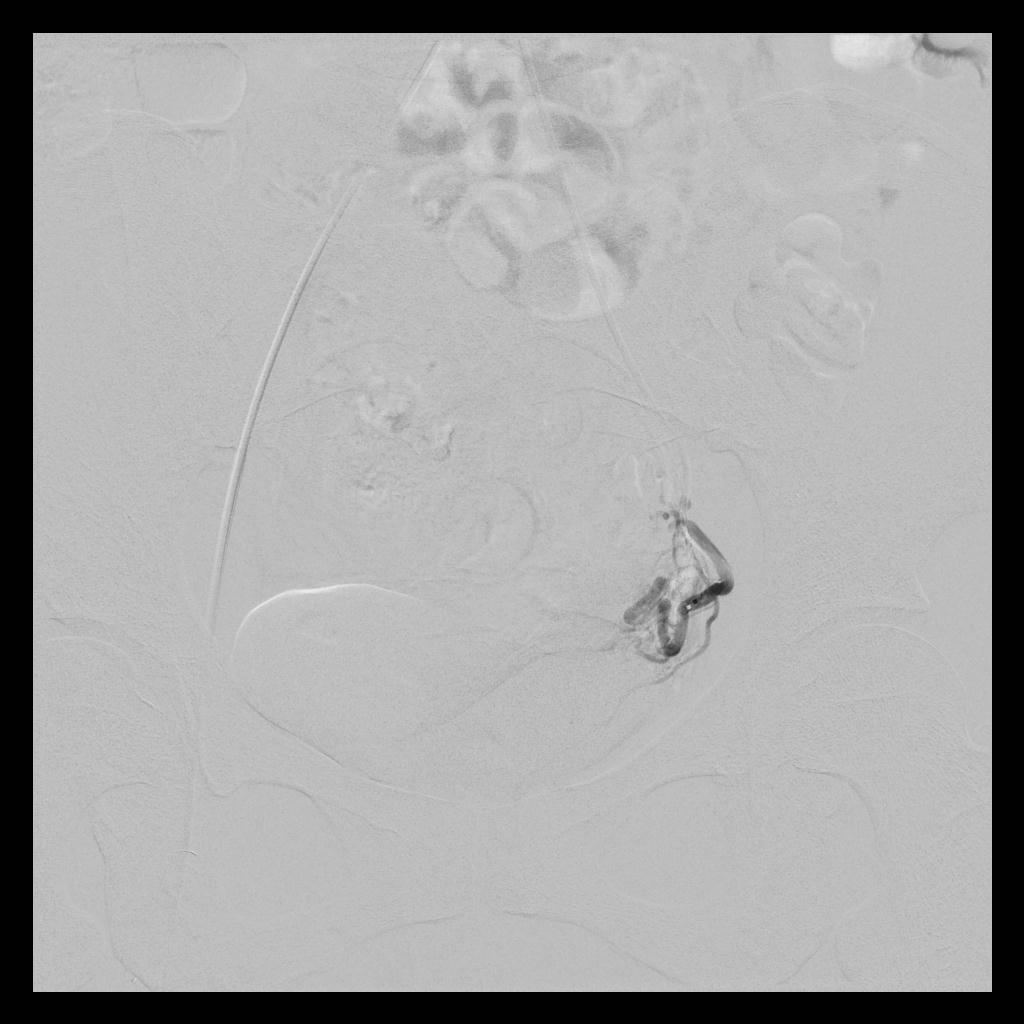

术后,经子宫动脉造影显示:之前增粗、迂曲、供血丰富的子宫动脉,经栓塞术后,血流基本停滞;之前增大的子宫和子宫肌瘤,经栓塞术后,其造影染色也已消失。

(左侧子宫动脉造影:术前、术后)